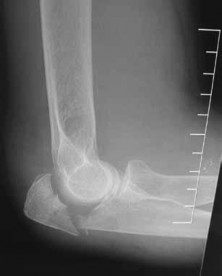

.Figures 11a and 11b show the radiographs of the open fracture of a 46-year-old man who injured his elbow on his nondominant arm in a motorcycle crash. On the day of injury, he underwent irrigation and débridement of the fracture. He was also treated with antibiotics. Which of the following definitive treatment methods will most likely lead to the best functional outcome?